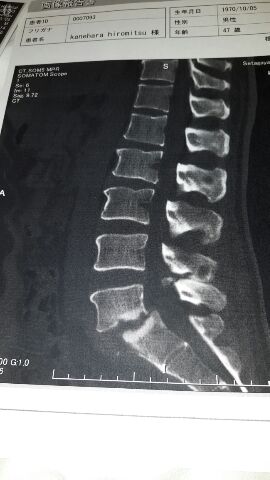

入院して今日で2ヶ月。

今は毎日一生懸命リハビリしてるよ。

現在、5分歩けるようになって、柔らかくて背もたれのある椅子なら15分ぐらい座れるようになった。

そして病院のリハビリとは別に、自分で加圧ベルトを巻いてしっかり筋トレにも励んでいます。

ドクターに、骨が固まるまであと2ヶ月かかり、6ヶ月は運動はできませんってこの前言われたから、もしかするとお正月は病院かな〜。

格闘技指導はいつからできるかな〜。